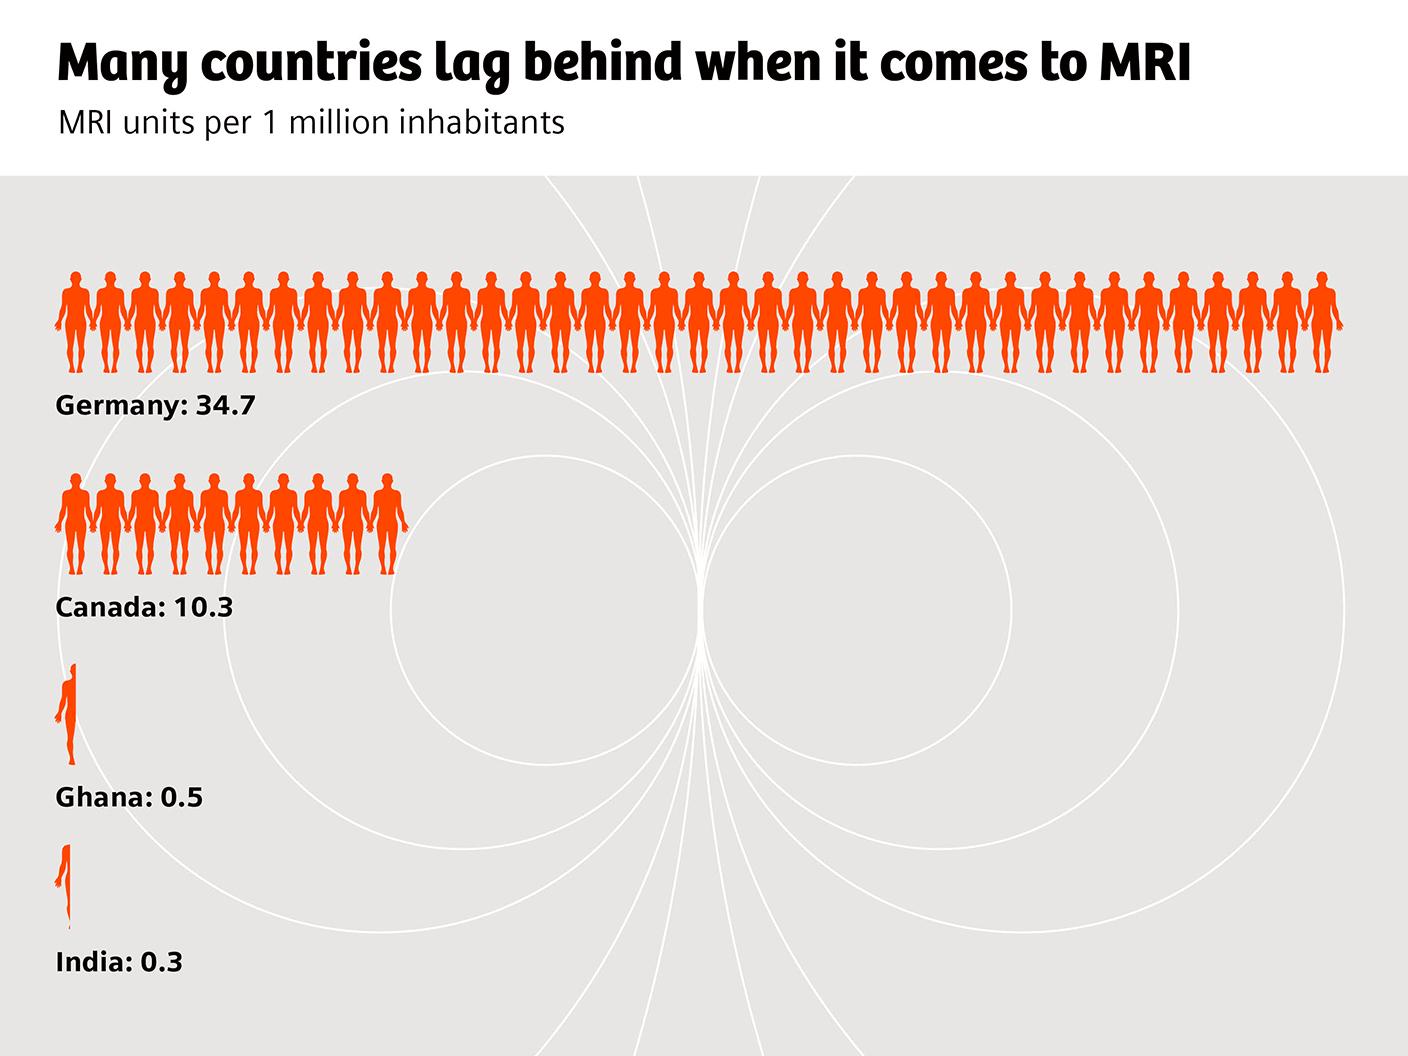

The challenge of accessibility

Despite its strengths, MRI is far from being universally accessible. In the OECD countries, for example, on average more than twice as many CT examinations as MRI scans are performed per 1000 inhabitants. Waiting times for an MRI scan are usually much longer than for a CT. There are also huge geographic variations: in Germany and Austria, the annual number of MRI examinations is bigger than the number of CT scans. In most other OECD countries, it is the other way round, and in less developed countries, the density of MRI scanning units is generally very low.